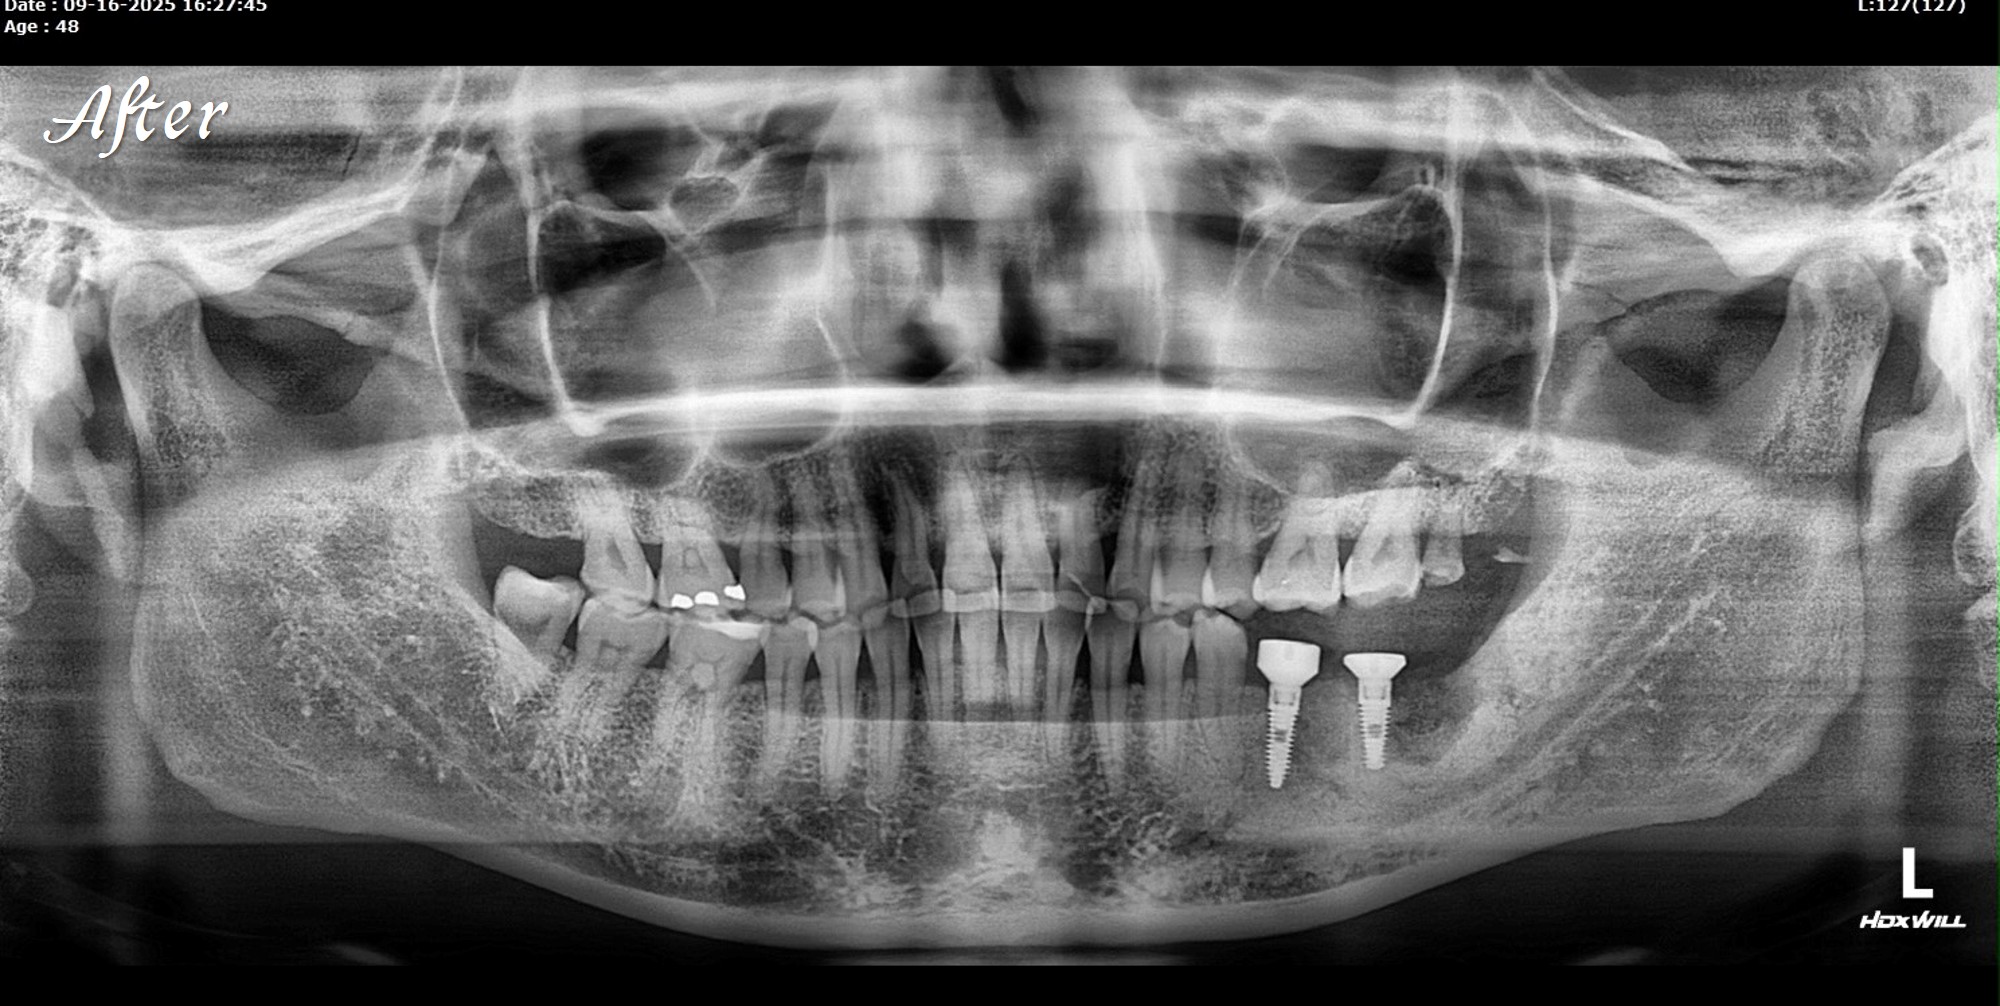

精奈創一鑽植牙系統團隊|3.5個月完成的植牙案例

一位初診新患者,陳博士評估後進行治療。

植牙後約3.5個月骨整合完成,骨頭穩定生長良好。

陳博士的治療方式,手術過程中不使用人工膜,

僅以可吸收縫線(chromic gut suture))完成縫合。

植牙當天,scan body掃描就同步完成,流程一次到位。

接下來就是裝固定假牙。